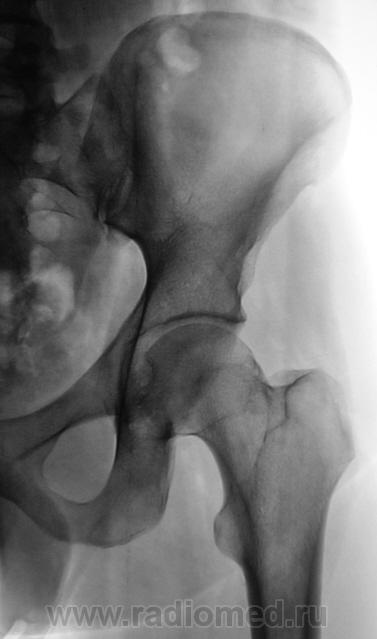

Пациент направлен на рентгенографию тазобедренного сустава с диагнозом ДОА.

очаг в подвертельной области - вряд ли артроз...

Наряду с очагом в головке, видится мне ещё и перелом - линейное нарушение кортикального слоя. И ещё очаг в крыле подвздошной кости (но может и придираюсь). Я бы взял изначально на МРТ таза и тазобедренных суставов.

Тут умеренная грибовидная чуть шейка укорочена...М-ть укладка сдрейфила и носками наружу уложили? никаких деструкций не вижу А в подвздошной кости газики ну итрохантер хорош